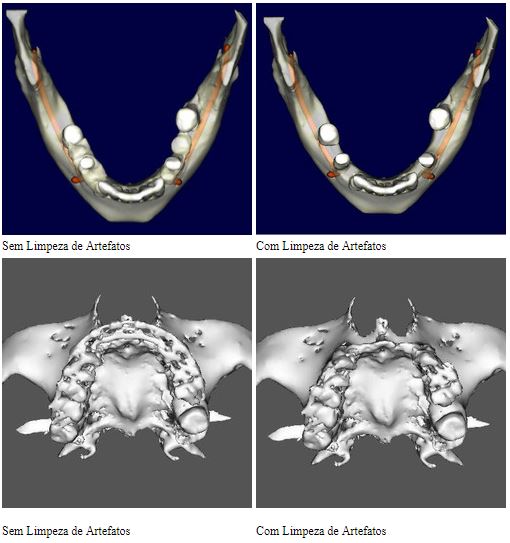

Limpeza de artefatos